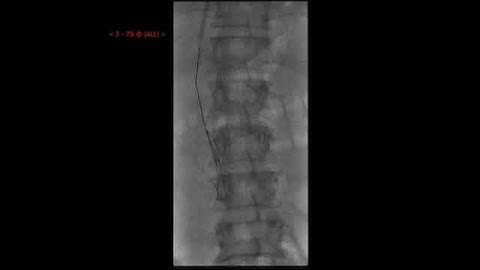

IVC filter retrieval